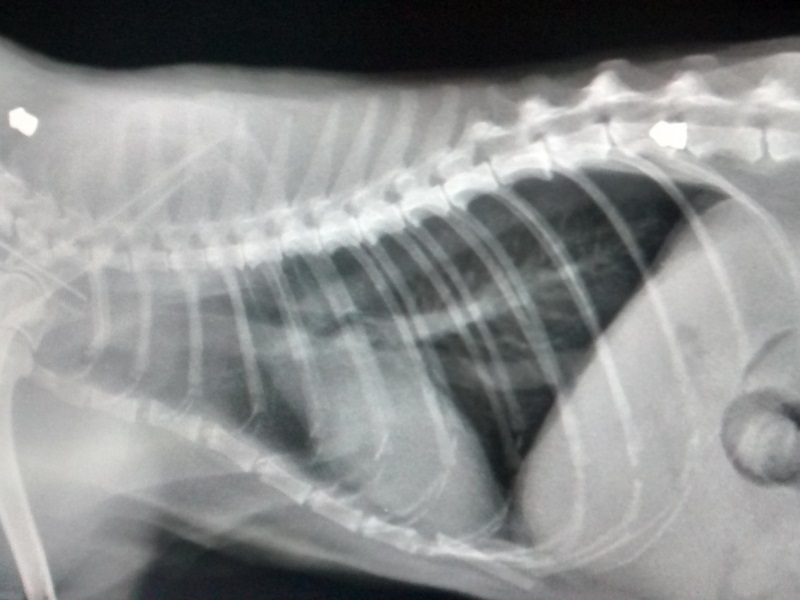

Для точной диагностики желательно провести компьютерную томографию, MRI (магнитно-резонансную томографию), а также (или хотя бы) рентгенографию позвоночного столба. Обязательно берется проба спинального ликвора (посредством пункции), так как анализ этой жидкости с высокой степенью достоверности позволяет выявлять различные виды воспалительных и инфекционных патологий.

Грыжа межпозвоночных дисков

Пожалуй, это одно из наиболее неприятных и серьезных заболеваний позвоночника, с которым приходится сталкиваться специалистам в своей практике. Что такое межпозвоночный диск? Это такая «амортизационная подушка», расположенная между позвонками. Каждый диск состоит из наружной, грубой и волокнистой, части, а также нежного центрального ядра, которое по консистенции отдаленно напоминает зубную пасту.

Межпозвоночные диски соединяют позвоночник в единое целое и позволяют ему быть гибким. Кроме того, они же амортизируют механические нагрузки, которым постоянно подвергается позвоночный столб. В случае, когда внешняя оболочка диска по каким-то причинам истончается, внутреннее его содержимое начинает выпячиваться в спинномозговой канал, пережимая спинной мозг или, в лучшем случае, отдельные его корешки. Это чрезвычайно опасный процесс, так как кот в любой момент может остаться полностью парализованным без особых шансов на исправление ситуации.